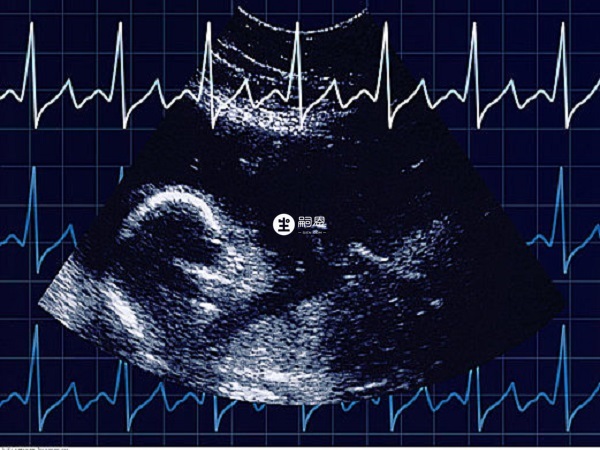

馬上就要進行移植了,我和老公都很緊張,所以想請問一下大家是移植5天的囊胚比較好還是6天的囊胚比較好呢?還是說需要結合其他什麼來一起看的?因為我們平時比較忙,所以想一次就成功,所以想先了解一下。從囊胚的培養天數來看,培養週期越短的,質量越好,也就是說5天的囊胚質量是最好的,其次是6天的囊胚。但需要注意的是,5天囊胚和6天囊胚的移植成功率並不是只看培養天數的,最終的成功率還要參考囊胚的分期和評級。因此不建議單純依靠囊胚的天數來判斷其質量和成功率,因此除了這些因素以外,女性的身體狀況也是十分重要的。

5天的囊胚就就是指培養到第五天發育到囊胚期的胚胎,6天囊胚就是培養到第六天才發育到囊胚的,僅從培養天數來看一般來說5天囊胚比較好,但實際上5天6天囊胚的區別並不是很大,關於5天囊胚和6天囊胚的質量分析如下: